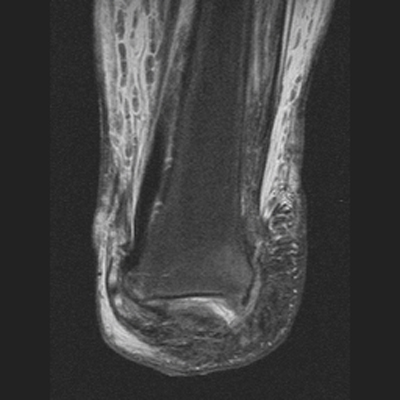

The MRI images below demonstrate the level of the Symes amputation along with bony and

soft tissue changes. Note the thick heel pad forming the majority of the distal

stump: the principle advantage of this procedure due to the more effective weight bearing.